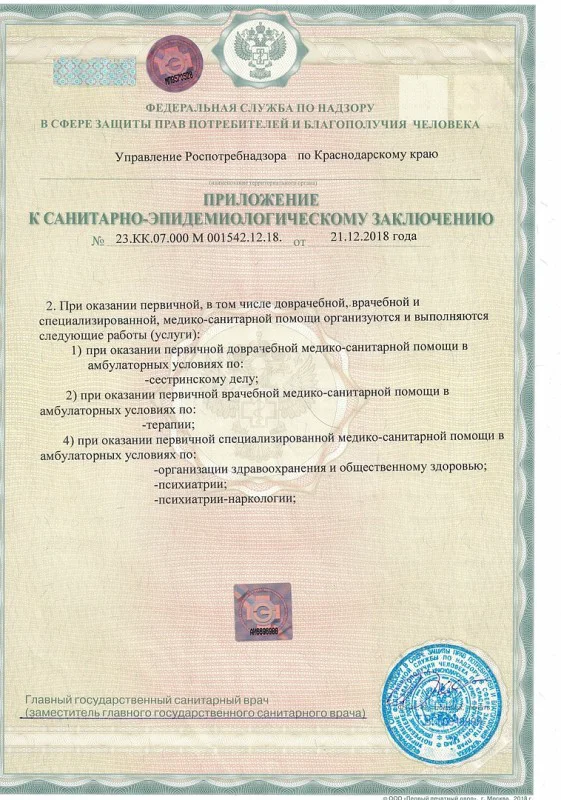

Лицензия на осуществление медицинской деятельности

Лицензия на осуществление медицинской деятельности

Лицензия на осуществление медицинской деятельности

Лицензия на осуществление медицинской деятельности

Лицензия на осуществление медицинской деятельности

Лицензия на осуществление медицинской деятельности

Лицензия на осуществление медицинской деятельности

Лицензия на осуществление медицинской деятельности